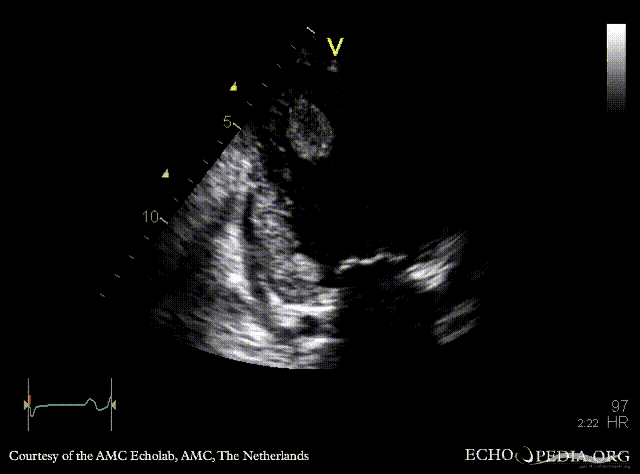

Case 142